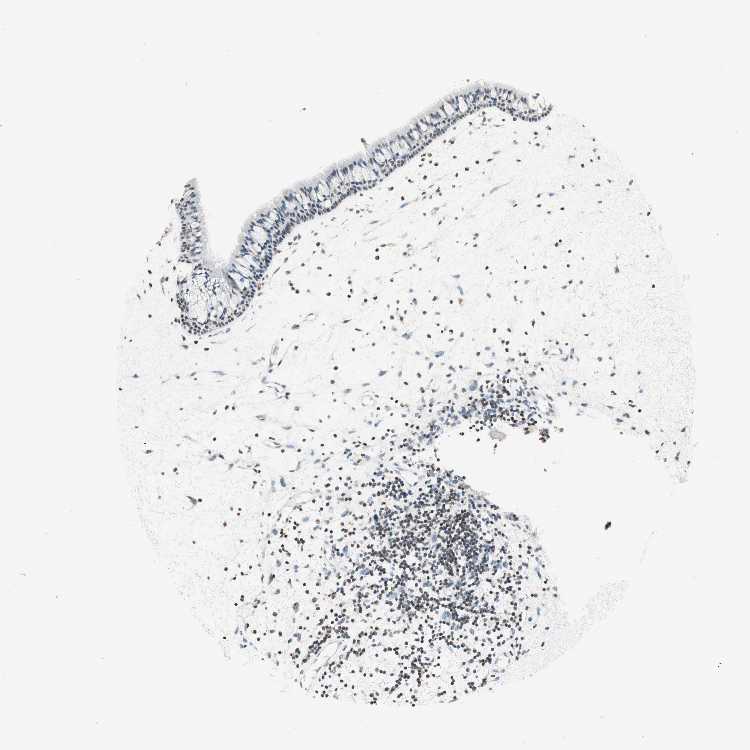

TISSUE PRIMARY DATA NASOPHARYNX Show tissue menu

NASOPHARYNX - Antibody stainingi

Antibody staining in the annotated cell types in the current human tissue is reported as not detected, low, medium, or high, based on conventional immunohistochemistry profiling in selected tissues. This score is based on the combination of the staining intensity and fraction of stained cells.

Each image is clickable and will lead to virtual microscopy that enables deeper exploration of all samples and also displays staining intensity scores, fraction scores and subcellular localization as well as patient and tissue information for each sample.

Antibody HPA003739Antibody CAB009737

Respiratory epithelial cells Not detectedNot detected